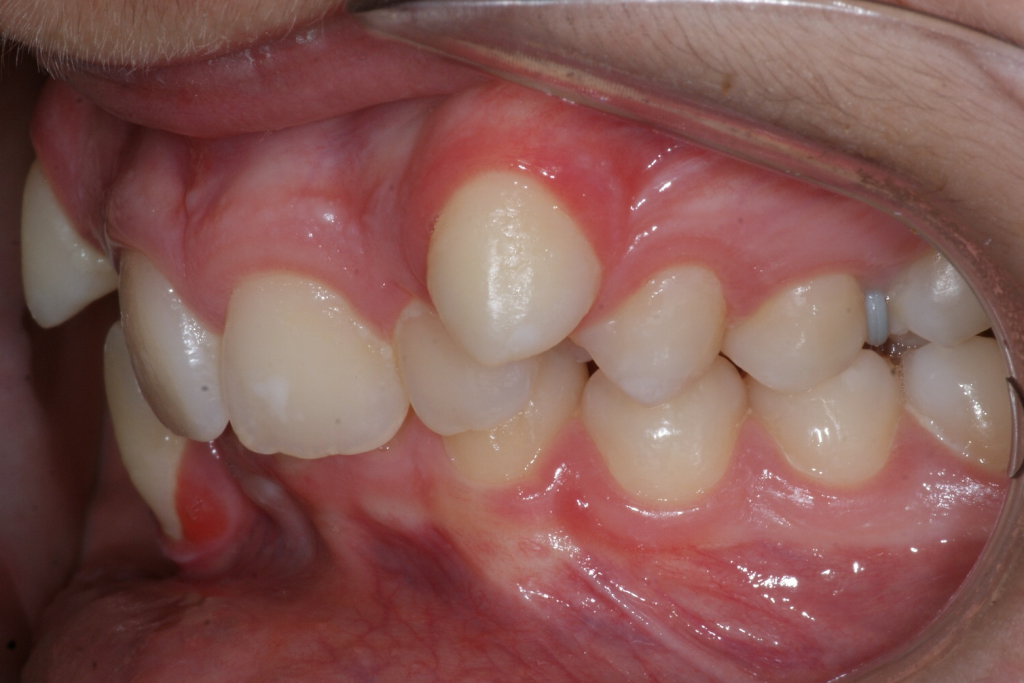

Correction d’une malocclusion de type Classe II avec chevauchement sévère aux 2 arcades. Des appareils fixes (boîtiers), une expansion palatine et l’extraction de 4 prémolaires (#14-24-35-45) furent nécessaires pour améliorer ce sourire. Traitement chez un adolescent, réalisé en 28 mois.